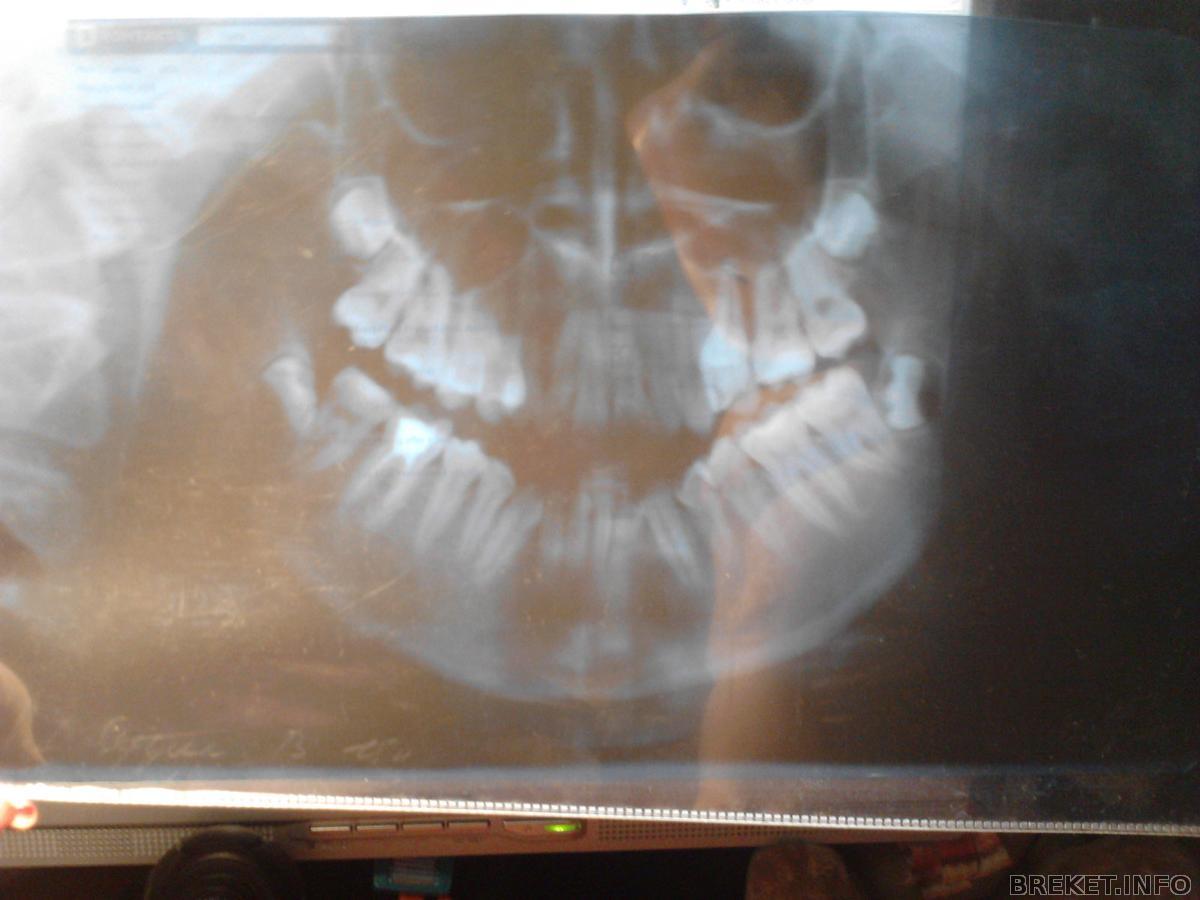

вот снимок мой, качество фотки не очень хорошее, у мпня по-другому, к сожалению, не получается(

подскажите что произойдет с моими мудростями?

мне их удалять надо? рецидив будет, если не удалить вовремя?

и когда, то самое время их удалять?

снимок.jpg